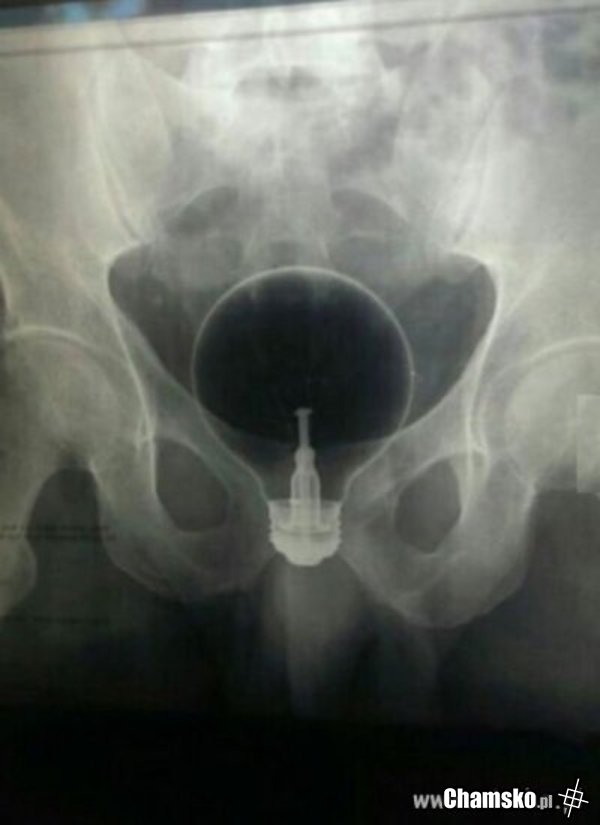

Zgadnijcie co to